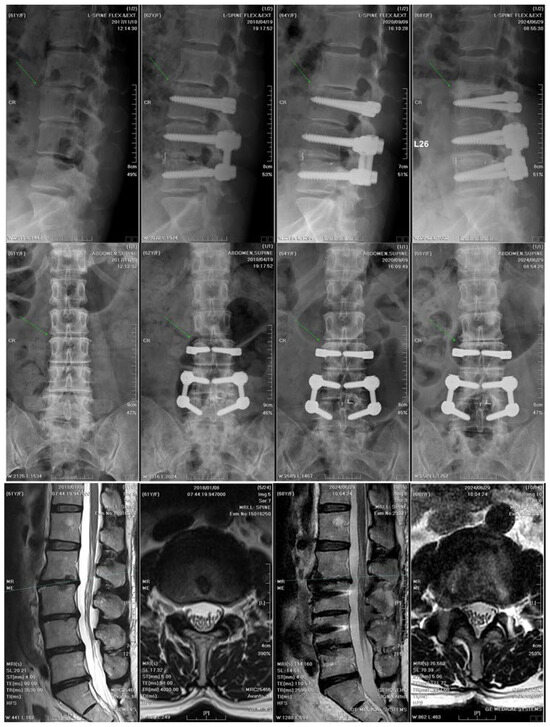

Lumbar spine surgery addresses degenerative conditions such as disc disease, stenosis, facet arthrosis, and deformities often extending into the thoracic spine. When conservative care fails or neurological deficits develop, surgery—including decompression, fusion, deformity correction, and motion preservation—is essential.

- Fusion strategies and instrumentation

- Motion preservation procedures

- Deformity correction in lumbar and thoracolumbar spine